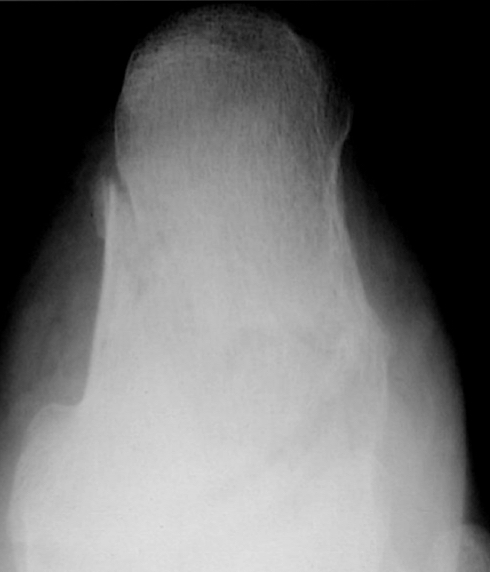

Torus fracture

lacks smooth margin